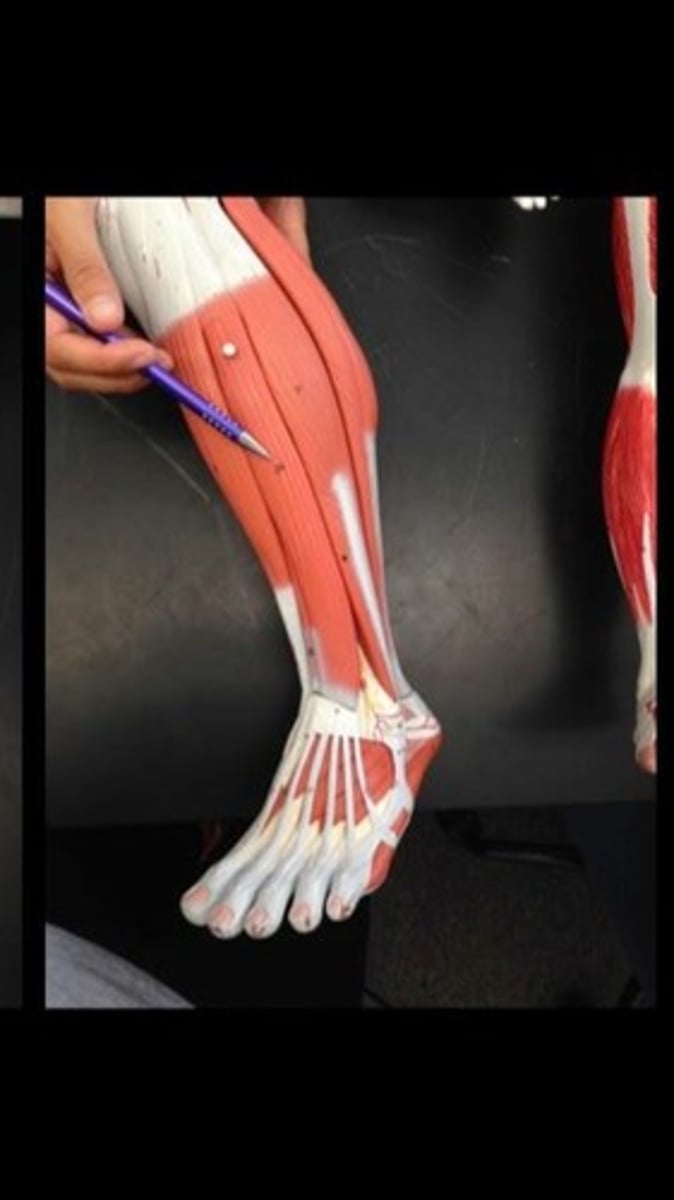

Tibialis anterior

Extensor digitorum longus

Fibularis longus

Extensor digitorum brevis of foot

Abductor digiti minimi of foot

Flexor digitorum brevis

Abductor hallucis